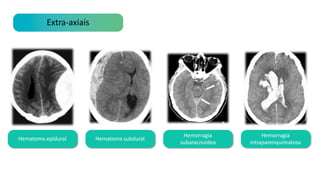

Lesões extra-axiais vs intra axiais

Extra-axiais Intra-axiais

Extra-axiais

Hematoma epidural Hematoma subdural

Hemorragia

subaracnoidea

intraparenquimatosa